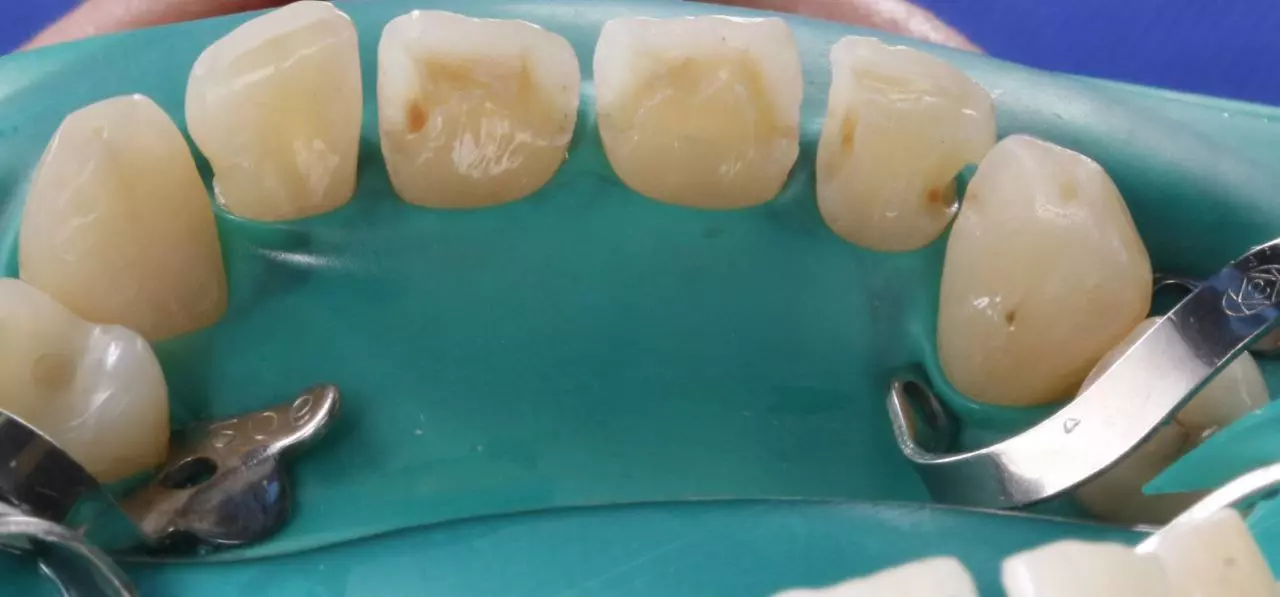

Художня реставрація 13.12.11.21.22.